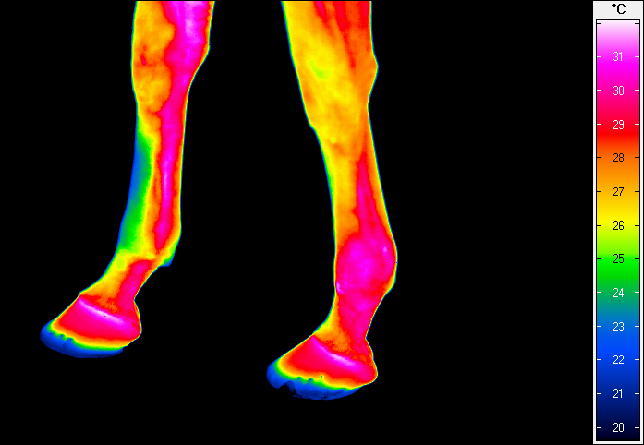

Termografia umożliwia nieinwazyjny pomiar rozkładu temperatury na powierzchni ciała konia. Wynikiem badania jest obraz – termogram, w którym poszczególne barwy odpowiadają określonym zakresom temperatur. Uzyskany rozkład cieplny odzwierciedla przede wszystkim ukrwienie tkanek powierzchownych, aktywność metaboliczną mięśni oraz właściwości izolacyjne skóry i okrywy włosowej.

W warunkach prawidłowych rozkład temperatury ciała konia charakteryzuje się wysokim stopniem symetrii pomiędzy lewą i prawą stroną. Najwyższe wartości temperatur obserwuje się w okolicach dobrze unaczynionych, takich jak oczy, nozdrza czy większe masy mięśniowe, natomiast najchłodniejsze obszary obejmują dalsze odcinki kończyn. Odstępstwa od tego wzorca – zwłaszcza asymetrie przekraczające około 1°C – mogą wskazywać na zaburzenia fizjologiczne lub rozwijające się procesy zapalne.

W medycynie weterynaryjnej i fizjoterapii najszersze zastosowanie termografia znalazła w ocenie dalszych odcinków kończyn, które są szczególnie narażone na urazy w trakcie treningu i użytkowania sportowego.

Metoda ta pozwala na identyfikację obszarów o podwyższonej temperaturze, związanych z zapaleniem ścięgien, więzadeł, torebek stawowych czy okostnej, często jeszcze przed pojawieniem się wyraźnych objawów klinicznych. Oprócz kończyn, istotnym obszarem zastosowania termografii jest grzbiet konia. Zaburzenia w obrębie mięśni przykręgosłupowych, więzadeł nad- i międzykolcowych czy stawu biodrowo-krzyżowego często mają charakter złożony i nie zawsze są łatwe do jednoznacznego rozpoznania przy użyciu standardowych metod. Termografia umożliwia wizualizację zmian w aktywności cieplnej tych struktur, co może wskazywać miejsca przeciążenia, bólu lub kompensacji ruchowych.